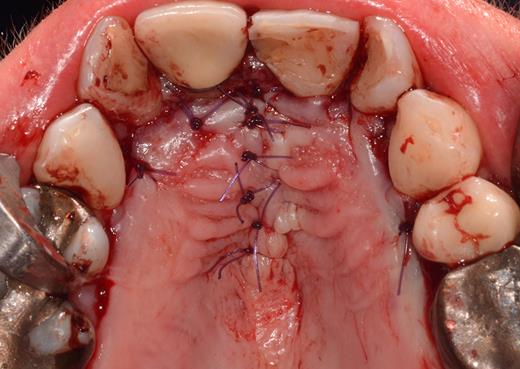

After a sulcular incision on the palatal side from teeth 15 to 25 and an incision in the midline of the palate omitting the incisive papilla and the two orifices of the NPD, two full-thickness mucoperiosteal flaps were raised. Thereafter, the incisive papilla and the whole contents of the incisive canal were enucleated (Figs 4–6). The bony incisive canal was filled with autologous bone harvested from the palatal region (bone scraper) (Fig. 7). A tension-free primary wound closure was achieved by moving the palatal flaps to the midline using single button and interdental vertical mattress sutures (Monocryl 4-0, Ethicon, Johnson & Johnson, USA) (Fig. 8). To avoid wound dehiscence and hematoma, an iodoforme gauze and a palatal plate were applied (Fig. 9). The patient was instructed to rinse three times a day with 0.1% chlorhexidine (formula hospitalis) for 2 weeks postoperatively. Sutures were removed after 14 days.

Excised soft tissue contents of the incisive canal including the neurovascular bundle and the incisive papilla.